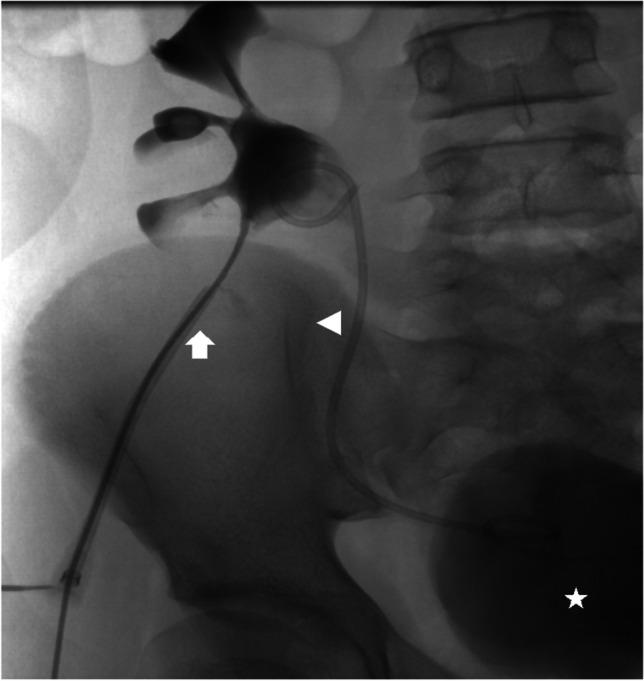

Imaging urolithiasis: complications and interventions in children.

Urolithiasis affects people in all age groups, but over the last decades there has been an increasing incidence in children. Typical symptoms include abdominal or flank pain with haematuria; in acute cases dysuria, fever or vomiting also occur. Ultrasound is considered the modality of choice in paediatric urolithiasis because it can be used to identify most clinically relevant stones. Complementary imaging modalities such as conventional radiographs or non-contrast computed tomography should be limited to specific clinical situations. Management of kidney stones includes dietary, pharmacological and urological interventions, depending on stone size, location or type, and the child's condition. With a very high incidence of underlying metabolic abnormalities and significant recurrence rates in paediatric urolithiasis, thorough metabolic evaluation and follow-up examination studies are of utmost importance.